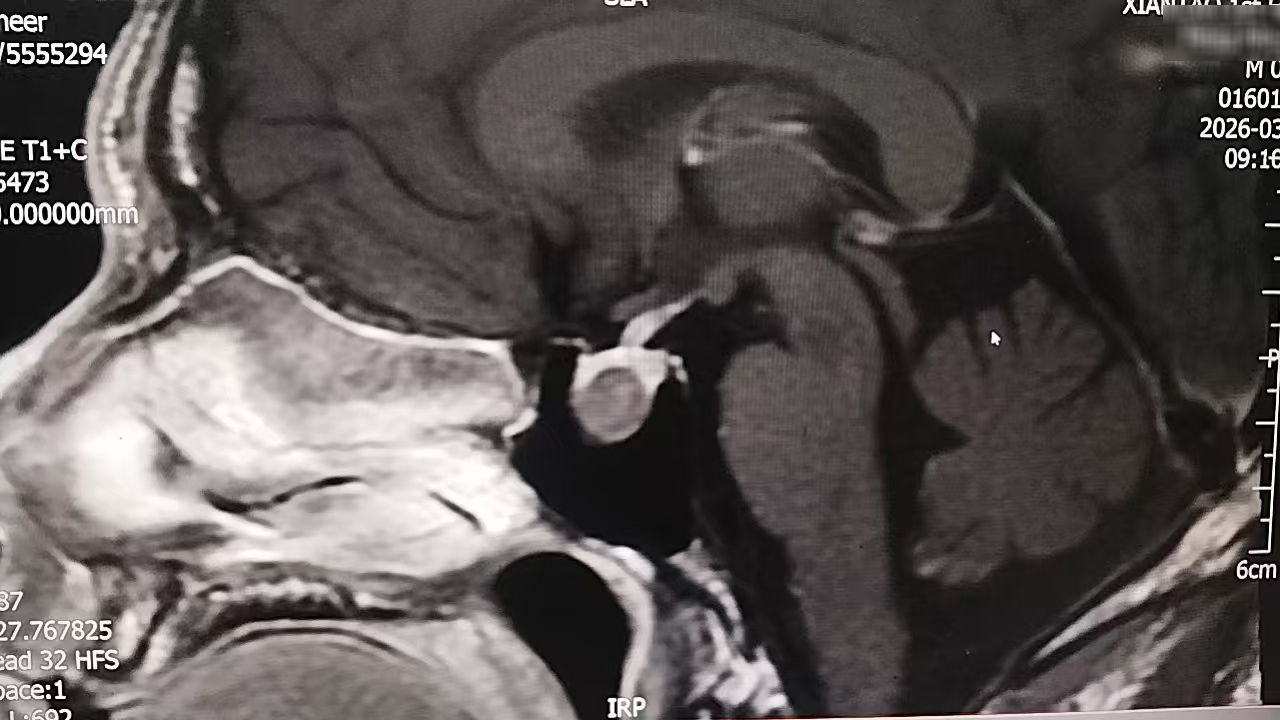

颅脑磁共振结果出来时,肖先生才知道,困扰他两年的“小毛病”,根源在颅内——鞍区占位。神经外科团队结合患者病史、体征及生长激素检验结果,最终确诊其为“垂体生长激素瘤”。

垂体瘤是起源于垂体前叶的常见颅内肿瘤,肖先生的肿瘤已侵犯鞍底硬膜。若不及时干预,不仅会持续加重头痛、内分泌紊乱,还可能引发视力视野损害等严重并发症。